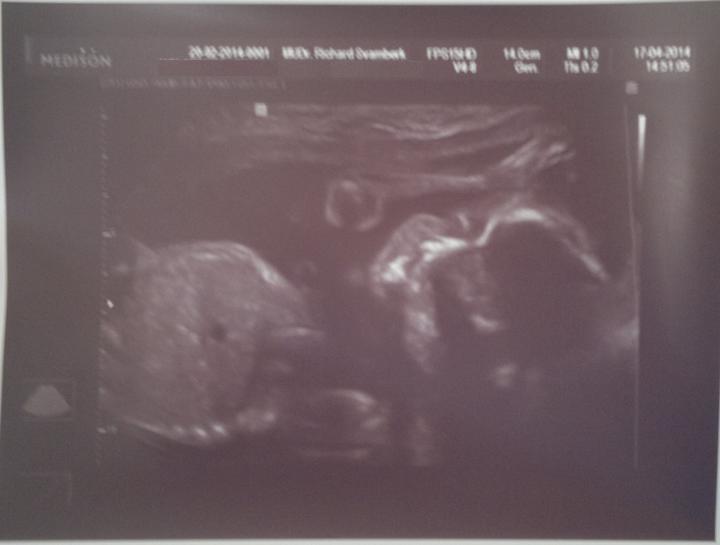

Jáchym Pavel Kolařík - 2. těhotenství

Termín porodu dle PM - 29. 8. 2014

( porod byl skutečně 24. 8. 2014 )